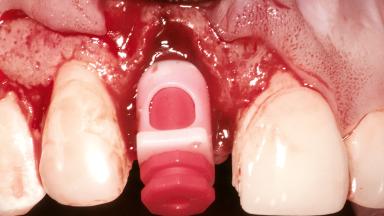

Replacement of a Maxillary Right Central Incisor Using an Early Loading Protocol

A healthy 26-year-old woman was referred for evaluation and treatment of her failing maxillary right central incisor (tooth 11). She reportedly traumatized the tooth at about age 9 and subsequently had repeated conventional and surgical endodontic procedures and fixed restorations. Despite these procedures, she had recurrent fistulas in the apical mucosa and a mid-facial pocket of 7 mm with suppuration. All other sites on the tooth probed 3 mm without inflammation. She presented with a medium biotype with triangularlyshaped teeth and a moderately high smile line, showing all of her papillas and a few millimeters of marginal gingiva in a full smile.Ceramic veneers were present on teeth 12, 21, and 22, and they were known to be somewhat bulky, eventually requiring replacement. She had a strong desire to avoid additional tooth preparation and would not consider a fixed dental prosthesis to replace tooth 11.